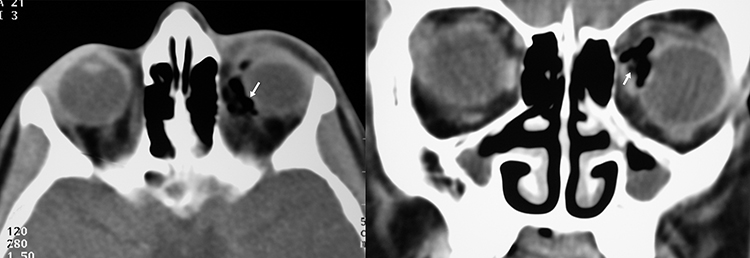

Figure 3.22.3: Axial and coronal computed tomography (CT) of an orbital wooden foreign body, read initially as orbital emphysema.

Note the squared-off scleral edge (arrow) on the axial image and the “stag horn” appearance (arrow) on the coronal image, both suggestive of retained orbital wood.